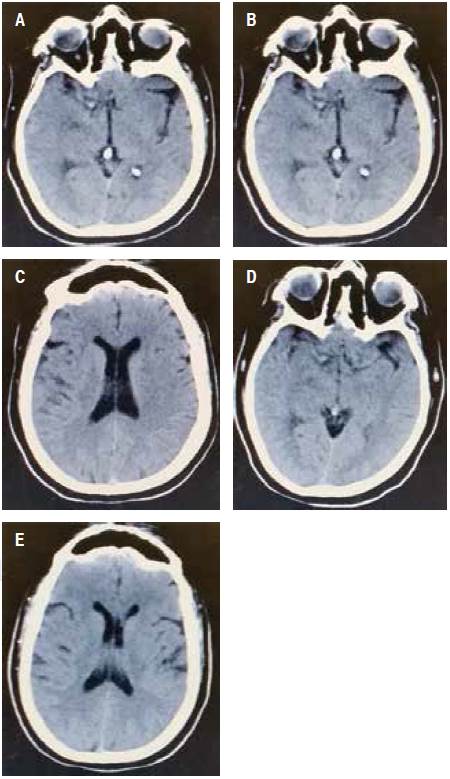

13:10 horas. Se le hizo una tomografía computarizada (TC) del cráneo, en la cual se apreciaron datos tempranos de isquemia, hiperdensidad de la arteria cerebral media derecha, así como pérdida de la relación sustancia gris-blanca (Figura 1).

Figura 1 (A-E) Tomografía axial computarizada simple (TC). Se muestra hiperdensidad de la arteria cerebral media derecha, así como pérdida de la relación sustancia gris-blanca.